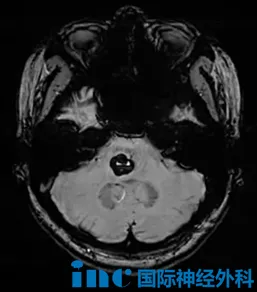

7岁的萌萌,2024年底因脑干海绵状血管瘤出血陷入昏迷,救护车连夜将她转送至苏州大学附属儿童医院。"那时候感觉孩子随时都可能走掉。"在最危急的48小时内,巴特朗菲教授为她实施了手术,让她重新睁开了眼睛。如今,萌萌已经回到了课堂,学习和生活都恢复了正常。

27岁的婷婷,2025年4月因头晕、肢体麻木和复视就医,检查发现脑干海绵状血管瘤,当时选择了保守观察。此后数月,症状一度有所减轻,复查也提示出血在逐渐吸收,但间歇性的麻木感始终没有完全消失。直到2026年2月下旬,症状再度加剧,检查证实发生了二次出血。她辗转咨询了多家医院,得到的答复几乎如出一辙:手术风险极高,面瘫的可能性较大。年轻的她最终做出决定:不再被动等待,选择寻求巴教授主刀的示范手术。

同样罹患脑干海绵状血管瘤的37岁吴先生,在初次出血时出现了面部麻木、讲话含糊、右手无法握笔打字、左腿走路不稳等症状。起初,他也抱着保守观察的态度,希望血肿能够自行吸收。然而病情并没有给他留下等待的余地,短时间内症状持续恶化:无法正常行走,言语愈加混乱,视力也开始模糊。情况危急之下,他将最后的希望寄托于此次巴教授的示范手术。